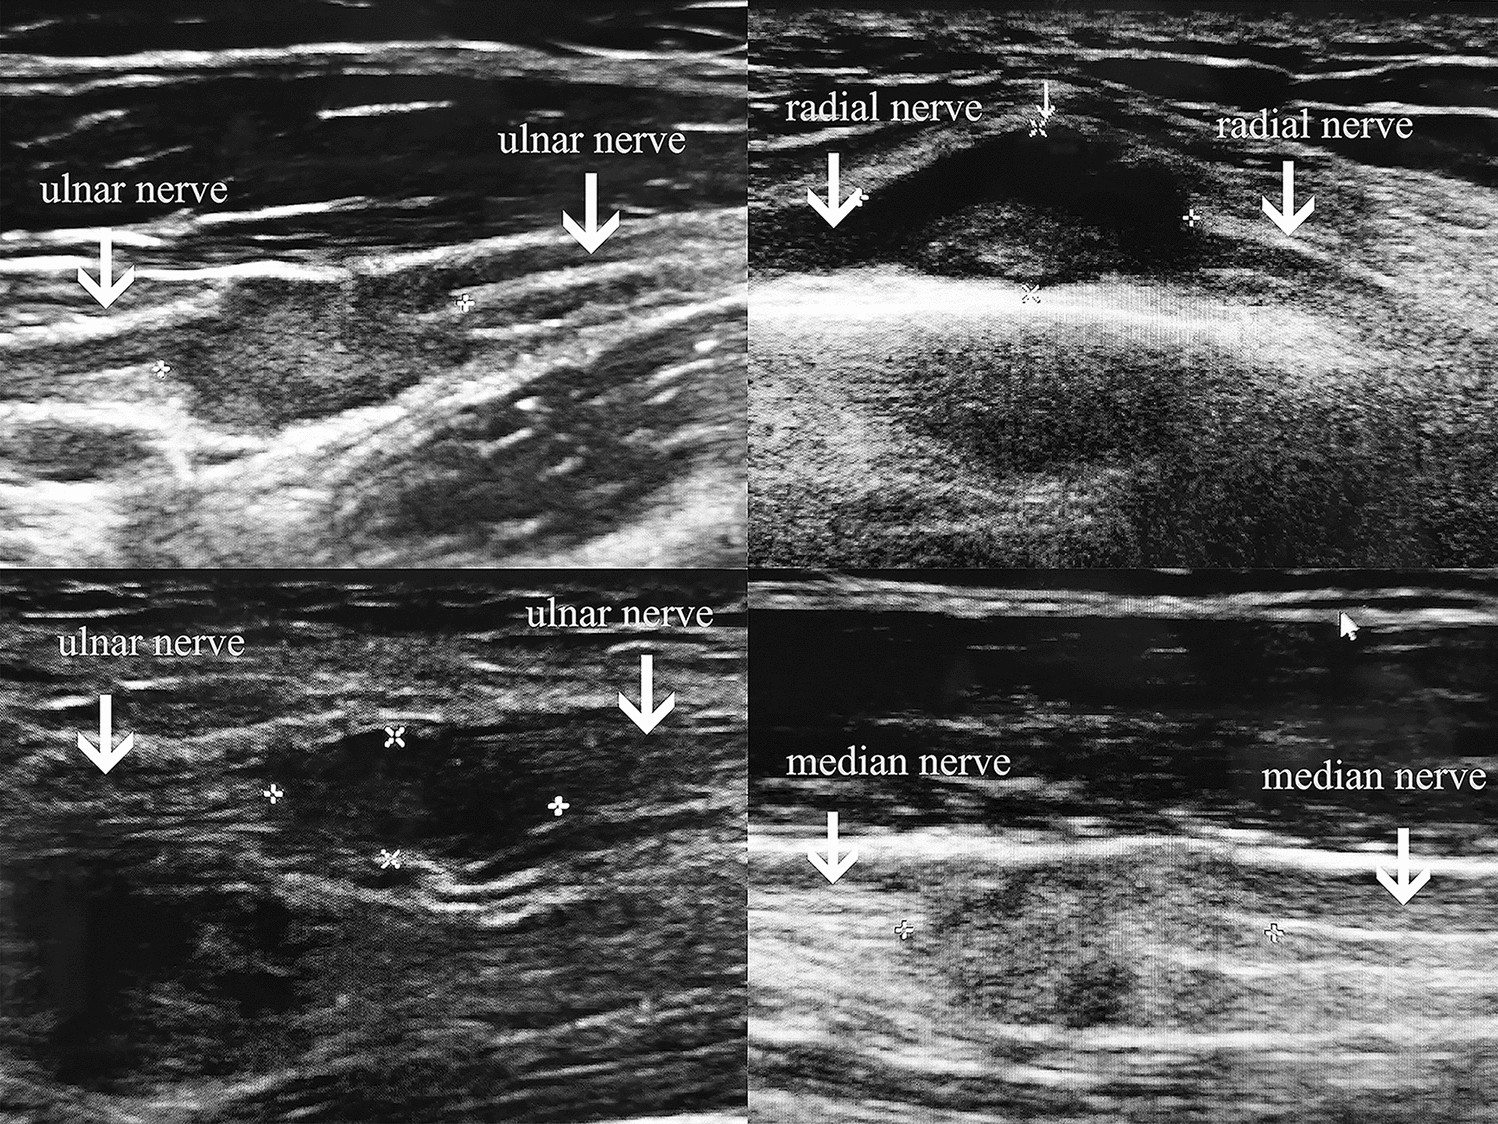

Fig. 1

From: The diagnosis and treatment of the epithelioid sarcomas involving the peripheral nerves

Preoperative high-resolution ultrasound images: The typical imaging data of the tumor and the peripheral nerve involved preoperatively shown by the high-resolution ultrasound.